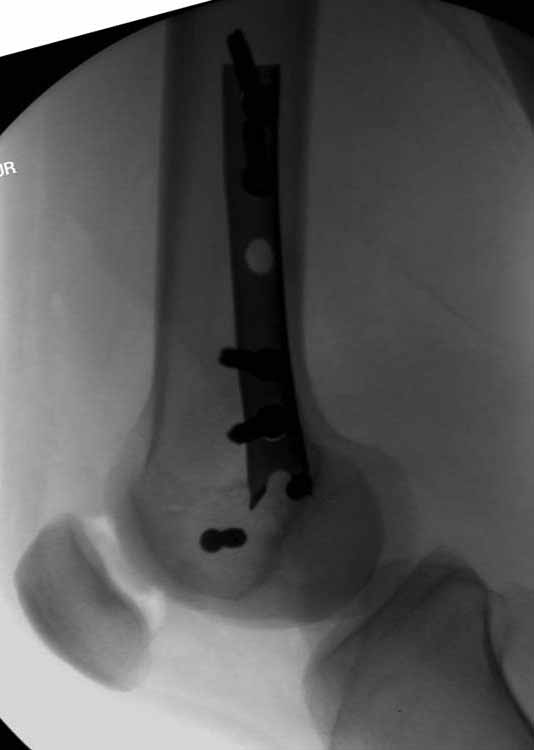

Ответ на эту часть Вашего поста – вложенный файл. Больная оперирована неделю назад по поводу открытого перелома дистального эпиметафиза бедренной кости. После операции она идёт в рентгенкабинет для выполнения послеоперационной контрольной рентгенографии, представленной на слайдах 10 и 11. Узнав, почему её фотографируют, просила передать Вам, Антон, привет.

В приложении пример недавней операции, C3, открытая репозиция, фиксация мыщелков спицами и винтами, ретроградный синтез большеберцовым гвоздем 10,5 мм диаметром, винты 5 мм.

Позволю себе напомнить коллегам ещё раз, что являюсь сторонником антеградного остеосинтеза при переломах дистального эпиметафиза бедренной кости. Такая приверженность основана не на преимуществах внесуставного введения стержня или большем проценте положительных результатов. Она основана на возможности обеспечить блокирование на минимальном расстоянии от суставной поверхности в нескомпрометированной кости и, таким образом стабилизировать максимально низкие переломы. В приведенном Вами случае самый дистальный из блокирующих винтов проведен на расстоянии более 2 см от конца стержня. Из-за того, что к стержню присоединяется кондуктор, на стержне теряется 1-1,5 см его длины, где можно было разместить отверстия для блокирования. И что более важно, вместе с потерянной для этой цели длиной стержня утрачивается для размещения блокировочных винтов, пожалуй, самая ценная часть дистального эпиметафиза бедренной кости. Проблемы дистального блокирования в разных плоскостях, локализации точки ввода стержня при антеградном остеосинтезе – это всё решаемые технические проблемы. Но антеградный остеосинтез низких дистальных переломов бедра при адекватном блокировании в нескомпрометированной кости обеспечивает решение стратегической задачи – стабильный остеосинтез и возможность нагрузки.